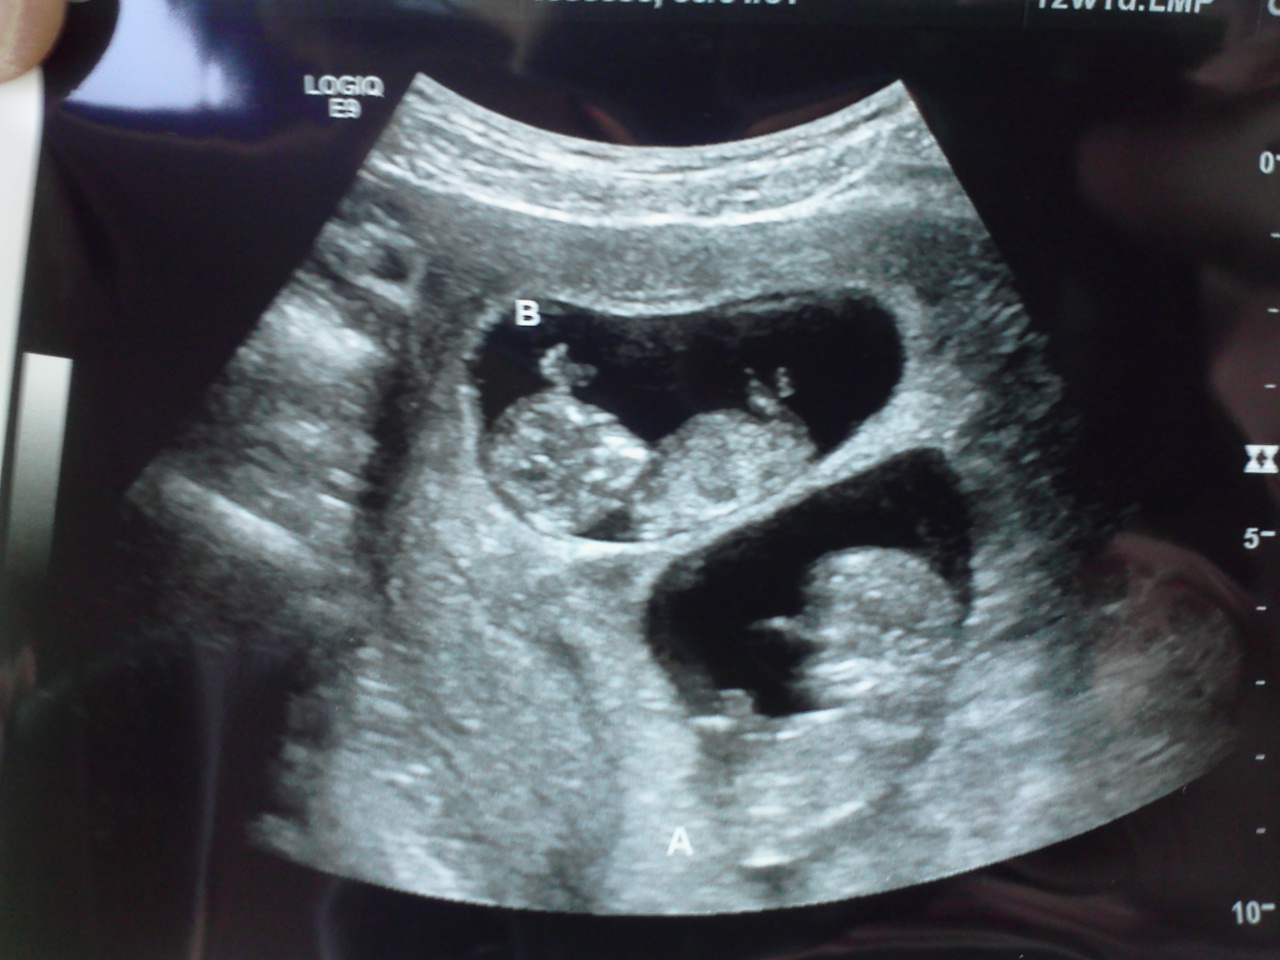

11 Week Ultrasound and Graduation Day!

Friday was a big day- I went in for lab work, another ultrasound, and had my first prenatal with the midwives.  The babies measured 11wks 1dy and 11wks 4dys and had strong heart beats.  After reviewing my results, the IVF doctor approved my coming off medication and graduated my care to the midwives.  Finally in my element. :)

We went in for our first 6.5 week ultrasound yesterday... twins! (Sorry for the no make-up picture; it was early and I've been dealing with morning sickness.)  They were curled up in a fetal position already and we saw both their little beating hearts.

The kids are excited that there are 2 babies in mom's tummy, even though they fully understand they are not ours.  I, myself, am super excited to be carrying twins.  I love the prospect of feeling them both move at the same time and of a twin home birth.  It's something I've always secretly aspired to... maybe this is why.